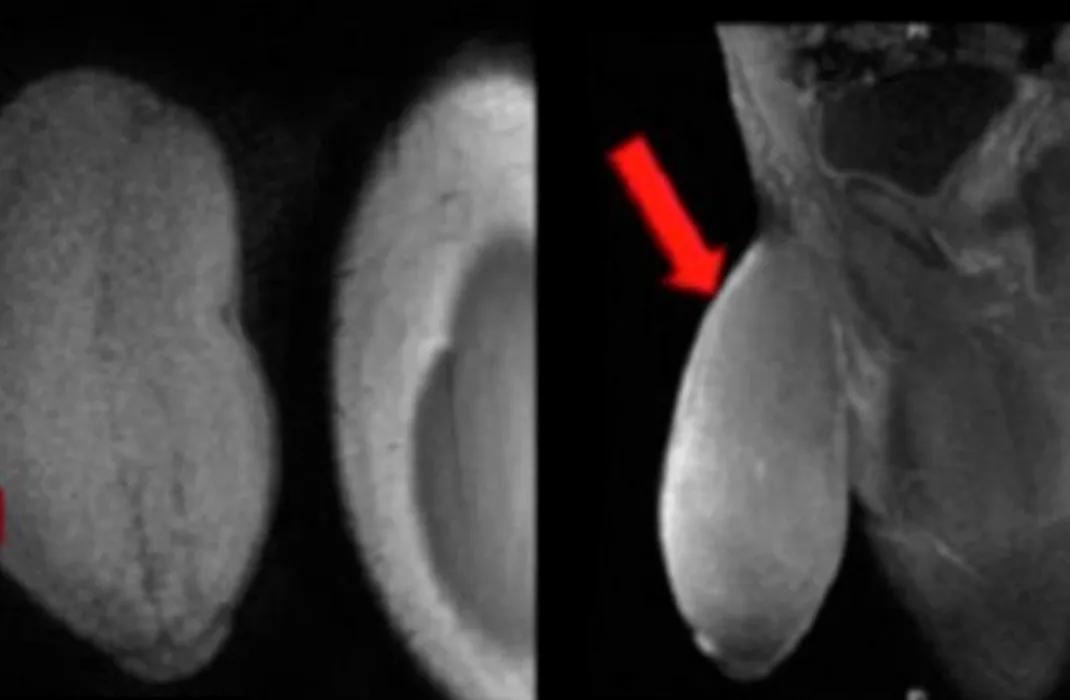

Un adolescent a suferit prima operație de reducere de penis cunoscută. Care este motivul